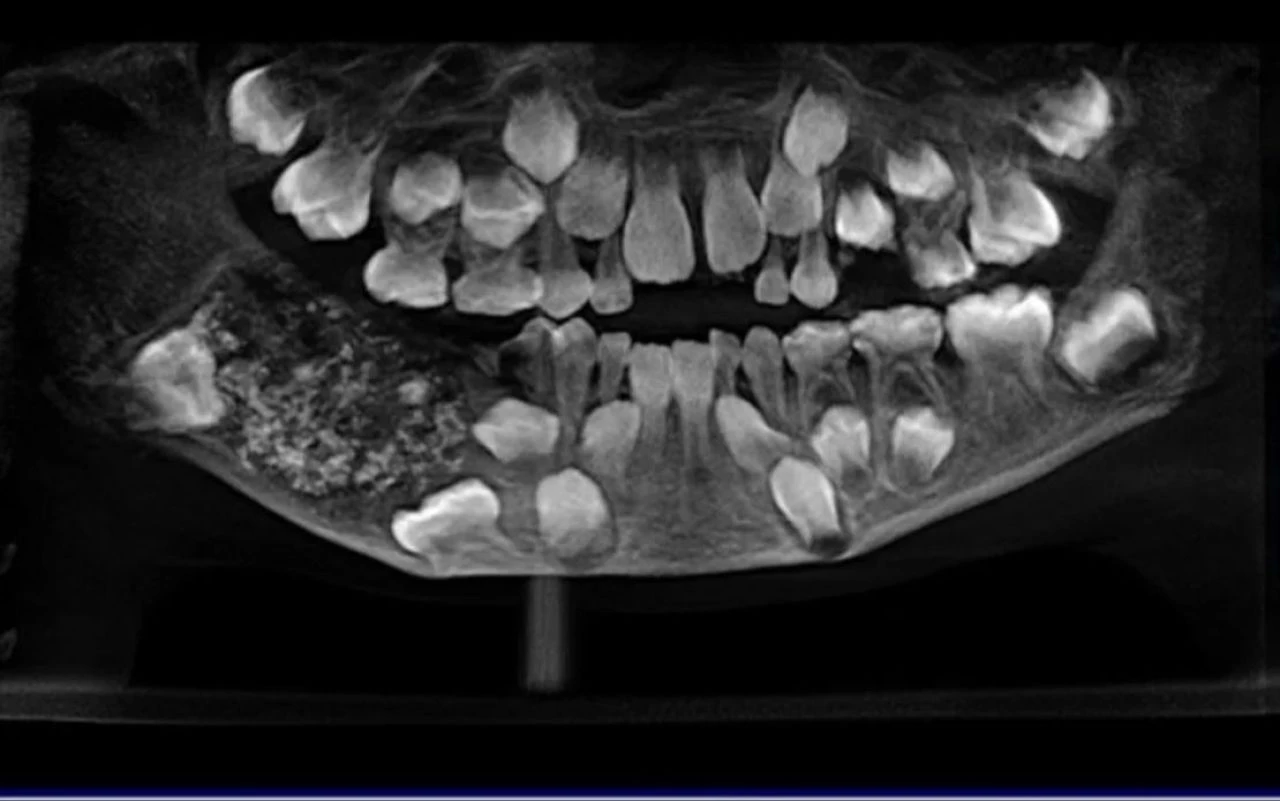

2019 yılında meydana gelen ve doktorları şoke eden vaka olarak kayıtlara geçen çocuğun çenesinden 200 gram ağırlığında ve 526 tane minyatür diş içeren bir kütle çıkarıldı. Çocukla ilgilenen sağlık personellerinin dişleri sayması ve incelemesi 5 saat sürdü.

Şaşırtan vaka hakkında yaptığı açıklamada, ''Boyutları 1 mm'den 15 mm'ye kadar değişen her dişte, mineyle kaplı ve kök benzeri yapıya sahip bir taç bulundu.'' ifadelerini kullandı.

Cerrahlar, odontoma olarak bilinen lezyonun genetik veya çevresel faktörlere bağlanabileceğini söyledi. Ulusal Biyoteknoloji Bilgi Merkezi'ne göre, odontomalar insanlarda genellikle yaşamlarının ilk yirmi yılında keşfedilirken, her yaşta ortaya çıkabiliyor.

Hastane, bunun "Dünya çapında belgelenen ve tek bir kişide bu kadar çok sayıda küçük dişin bulunduğu ilk vaka" olduğunu söyledi.